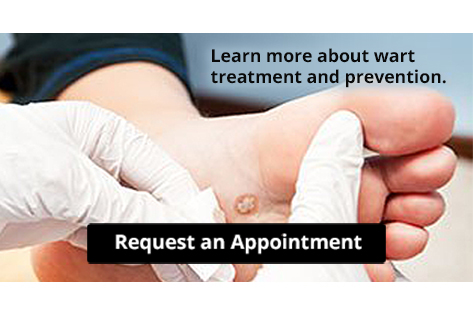

Plantar Warts Can Be Treated!

Plantar Warts Can Be Treated!Plantar warts are small growths that develop on parts of the feet that bear weight. They’re typically found on the bottom of the foot. Don’t live with plantar warts, and call us today!